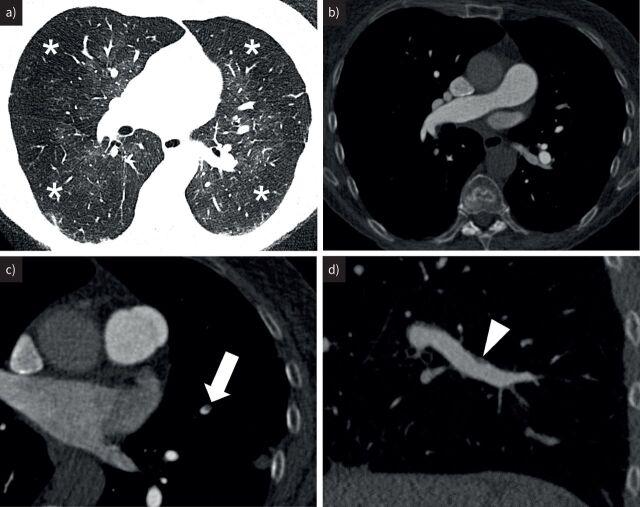

Chronic thromboembolic pulmonary hypertension (CTEPH) is a rare complication of acute pulmonary embolism. It is caused by persistent obstruction of pulmonary arteries by chronic organised fibrotic clots, despite adequate anticoagulation. The pulmonary hypertension is also caused by concomitant microvasculopathy which may progress without timely treatment. Timely and accurate diagnosis requires the combination of imaging and haemodynamic assessment. Optimal therapy should be individualised to each case and determined by an experienced multidisciplinary CTEPH team with the ability to offer all current treatment modalities. This report summarises current knowledge and presents key messages from the International CTEPH Conference, Bad Nauheim, Germany, 2021. Sessions were dedicated to 1) disease definition; 2) pathophysiology, including the impact of the hypertrophied bronchial circulation, right ventricle (dys)function, genetics and inflammation; 3) diagnosis, early after acute pulmonary embolism, using computed tomography and perfusion techniques, and supporting the selection of appropriate therapies; 4) surgical treatment, pulmonary endarterectomy for proximal and distal disease, and peri-operative management; 5) percutaneous approach or balloon pulmonary angioplasty, techniques and complications; and 6) medical treatment, including anticoagulation and pulmonary hypertension drugs, and in combination with interventional treatments. Chronic thromboembolic pulmonary disease without pulmonary hypertension is also discussed in terms of its diagnostic and therapeutic aspects.